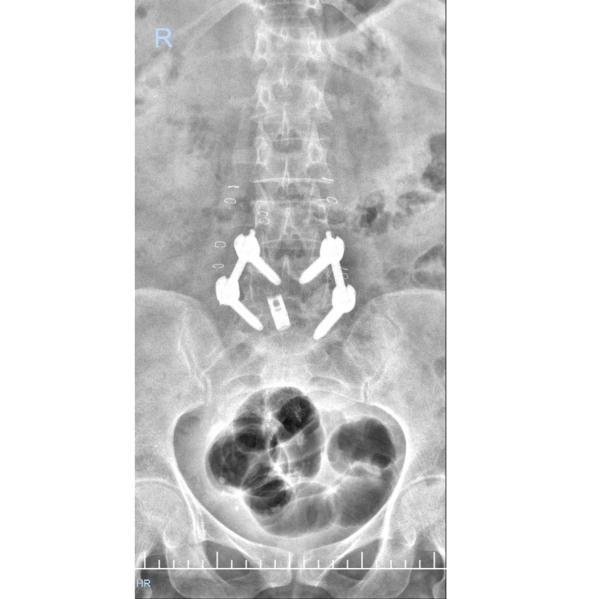

TLIF for L45 Spondylolisthesis This patient from ...

Endoscopic TLIF or Endo TLIF for L45 Spondylolisthesis